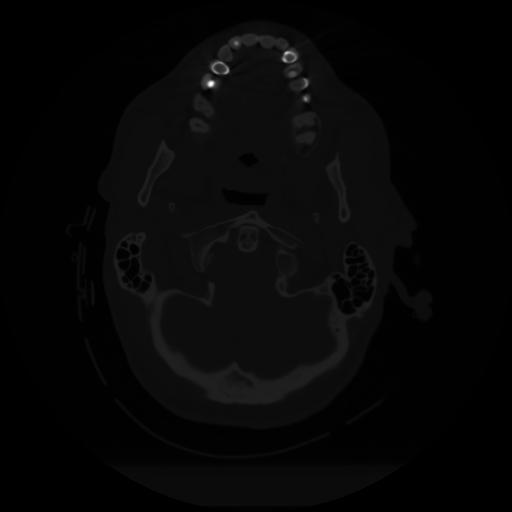

12 P.BLANDAS,,Vol,0.5,P.BLANDAS,,